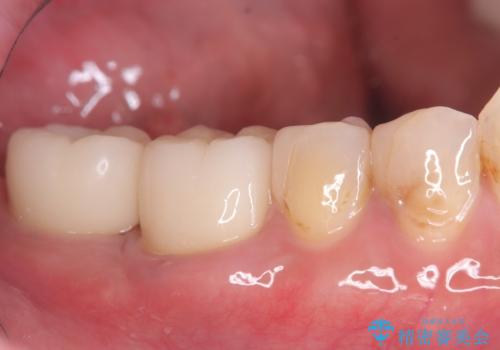

まず、右上6・右下6の根管治療を再度行い、根の状態をしっかり整えた上で、セラミッククラウンを装着しました。さらに、欠損していた右上7・右下7にはインプラントを埋入し、セラミッククラウンを装着。治療後は、「奥歯でしっかり噛めるようになり、不安なく食事ができるようになった」と患者様にも大変ご満足いただきました。